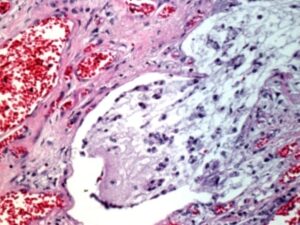

bronchi di un adulto colpiti da fibrosi cistica